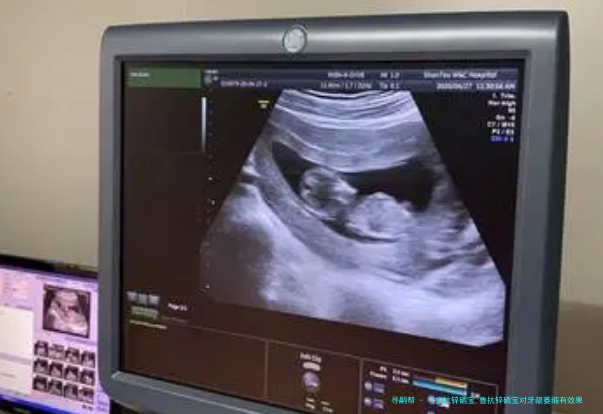

〖鲁抗锌硒宝,鲁抗锌硒宝对牙龈萎缩有效果吗?〗【】选择我们就等于选择了宝宝的降临,是为数不多的五A集试管服务中心,成功保您满意,为您最终达成试管心愿,是一家试管领先的服务公司,我们是一家专业从事试管助孕机构。